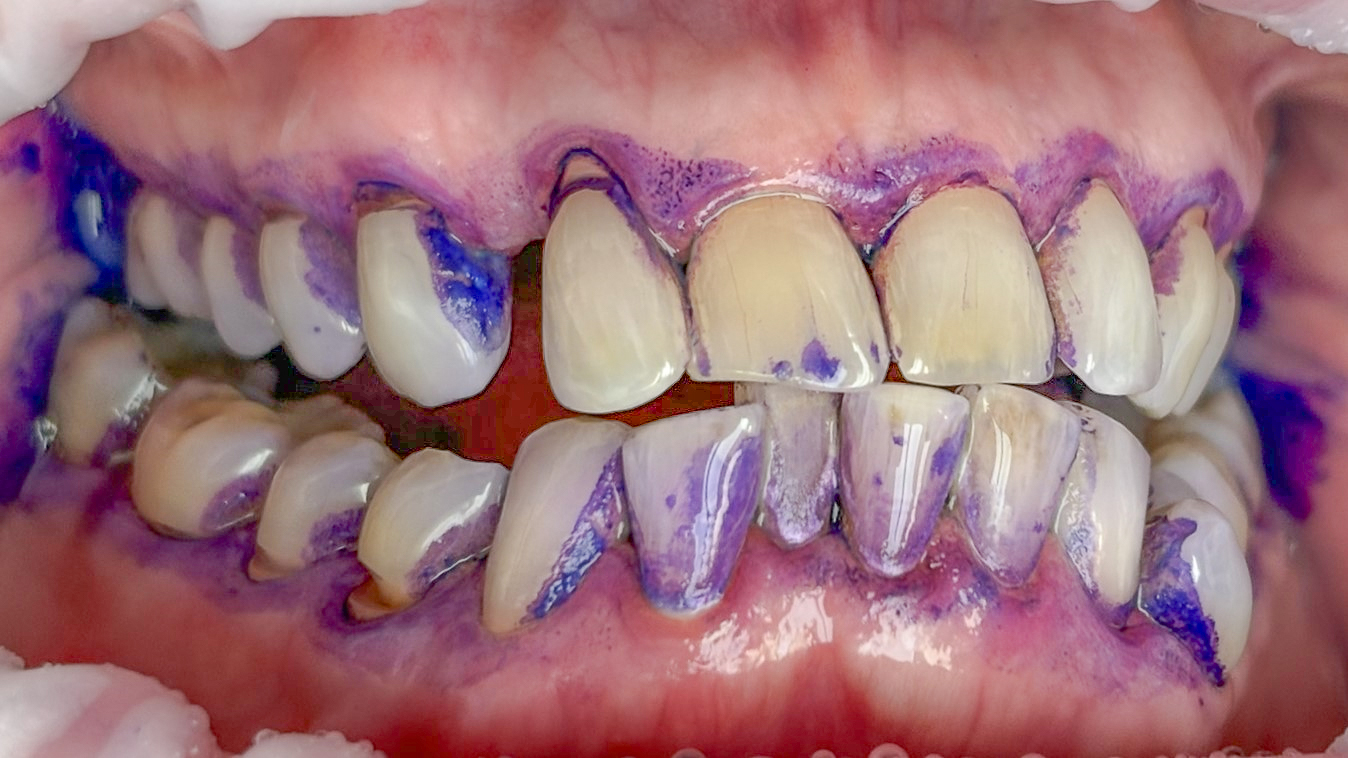

Bezüglich Methoden für das supragingivale Biofilm-Management wurden für spezielle Luft-Wasser-Pulver-Systeme („Airflowing“) im Vergleich zum konventionellen Vorgehen mit rotierenden Bürstchen und Pasten („Politur“) gleichwertige oder bessere klinische Ergebnisse gezeigt (27-29). Mit einem systematischen, modularen Protokoll für die primäre („PZR“) und sekundäre (AIT, UPT) professionelle Prophylaxe wird nach Spülen mit antiinfektiver Lösung und Befundaufnahme (Schritt 1), obligatorischem Anfärben und Patienteninstruktion (Schritt 2, Abb. 2) zunächst der Biofilm mit speziellen Luft-Wasser-Pulver-Systemen und dann erst verbleibender Zahnstein mit piezokeramischem Ultraschall entfernt (Schritte 4 bis 6, Abb. 3-5). Die sauberen Zahnoberflächen können dann optimal untersucht und ein risiko-adaptiertes Recall-Intervall festgelegt werden (Schritte 7 und 8 der Guided Biofilm Therapy GBT, Abb. 6) (27).